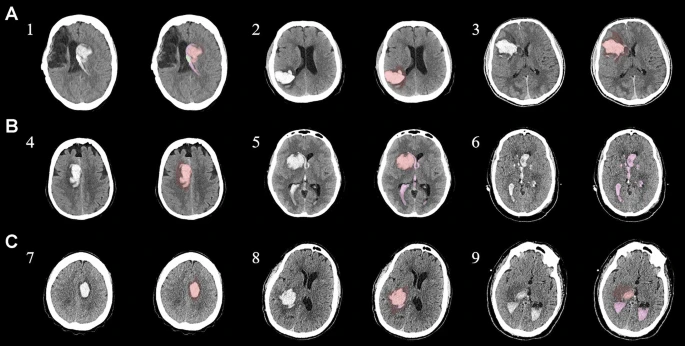

本研究纳入2018年1月1日至2020年10月31日发病168小时内发生急性ICH的患者。间充质干细胞被静脉注射给9名患者(5名女性,4名男性),平均年龄(范围)为61(36-84)岁。表1总结了人口统计学和临床特征 。出于描述目的,患者按照入组顺序获得编号,并连续分配到三组中的一组,每组三人。根据模型 2 分割,ICH体积范围为0.1至54.9mL(平均ICH体积为23.5mL)。5例ICH累及局部脑叶,其余则位于基底节或外囊深处。在三名患者中,ICH位于丘脑(图1),在一名患者中,血肿位于多个脑结构(即尾状核、壳核和苍白球)。平均而言,MSC在ICH后3天进行注射。

具有临床特征的探索性成像体积模型分析

ABC/2模型1和模型2分割方法通过ICH和IVH体积的线性回归显示出良好的相关性(图3a、b)。与模型2分割体积方法(例如,每个CT15-20分钟)相比,模型1ABC/2派生的半定量方法和改进的Graeb IVH方法完成时间较短(例如,2-5分钟)。有趣的是,NIHSS评分与IVH体积M2方法的比较显示出线性相关性(R 2 = 0.7217),并且当IVH小于20mL或大于20mL时,NIHSS评分似乎出现聚类(图3c)。PHE分析显示MSC注射剂量和PHE体积之间存在轻微的负相关关系。

a,通过模型1ABC/2派生方法与vol模型 2(分割)进行的神经影像ICH vol的线性回归。b、IVH通过模型1和定量分割模型2方法对Graeb进行了修改。c,出血量和NIHSS评分与IVH量通过分割进行比较。